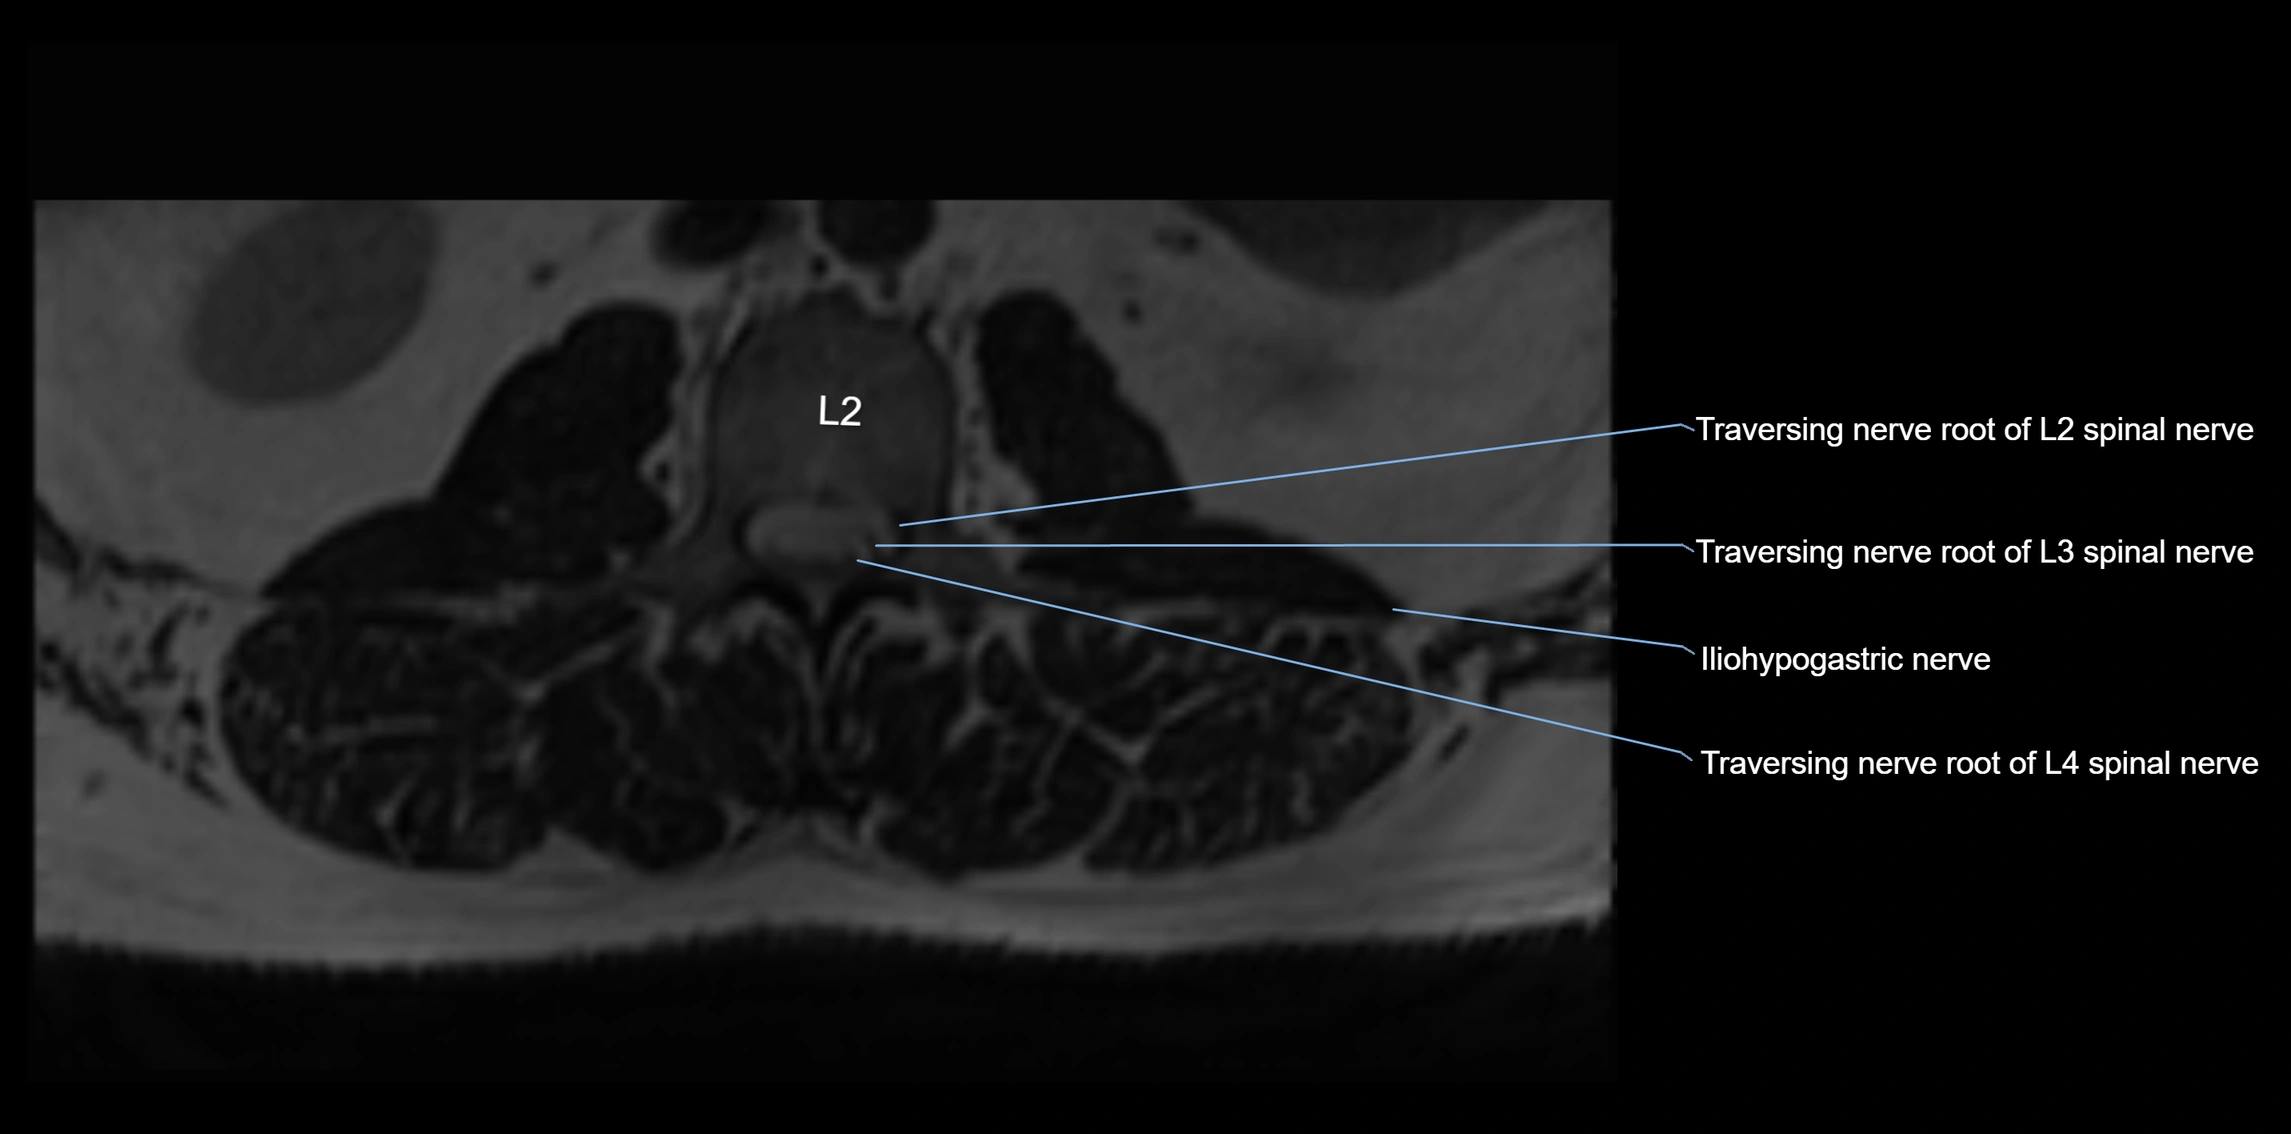

MRI Appearance

T1-weighted images:

• Nerve appears as a very thin low-to-intermediate signal intensity structure

• Surrounded by bright fat, aiding visualization

T2-weighted images:

• Nerve shows intermediate to mildly hyperintense signal compared to muscle

• Pathological involvement appears brighter

3D T2 SPACE / CISS:

• Nerve appears intermediate to mildly hyperintense compared to muscle

• Surrounded by bright fat or CSF, improving visualization

• Best sequence for mapping small pelvic nerves such as the anococcygeal